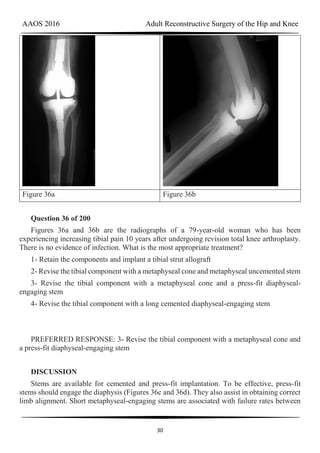

Figure 36a Figure 36b

Question 36 of 200

Figures 36a and 36b are the radiographs of a 79-year-old woman who has been

experiencing increasing tibial pain 10 years after undergoing revision total knee arthroplasty.

There is no evidence of infection. What is the most appropriate treatment?

1- Retain the components and implant a tibial strut allograft

2- Revise the tibial component with a metaphyseal cone and metaphyseal uncemented stem

3- Revise the tibial component with a metaphyseal cone and a press-fit diaphyseal-

engaging stem

4- Revise the tibial component with a long cemented diaphyseal-engaging stem

PREFERRED RESPONSE: 3- Revise the tibial component with a metaphyseal cone and

a press-fit diaphyseal-engaging stem

DISCUSSION

Stems are available for cemented and press-fit implantation. To be effective, press-fit

stems should engage the diaphysis (Figures 36c and 36d). They also assist in obtaining correct

limb alignment. Short metaphyseal-engaging stems are associated with failure rates between

AAOS 2016 Adult Reconstructive Surgery of the Hip and Knee

31

16% and 29%. Cemented stems may be shorter than press-fit stems because they do not have

to engage the diaphysis. Short, fully cemented stems offer the advantage of metaphyseal

fixation. Hybrid stem fixation makes use of the metaphysis for cement fixation with

metaphyseal cones or sleeves and diaphyseal-engaging press-fit stems.